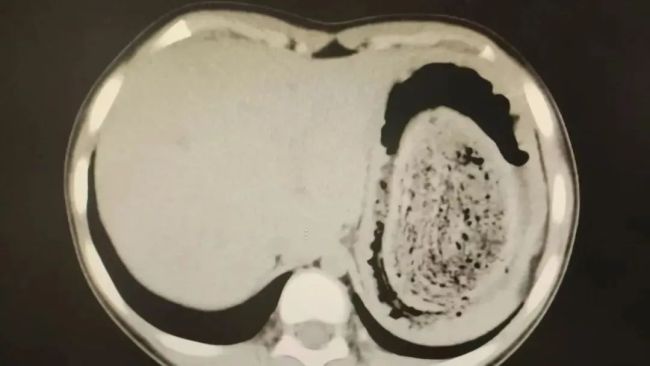

结果出来时,医生都惊呆了:小可的胃里,塞满了成团的头发,几乎占了胃容量的四分之三。大量不能消化的物质,在胃酸的作用下发生变性,并与食物及其他物质结合形成团块,慢慢变成坚硬的“胃石”。

为了避免用手术方式去除头发团,陈攸涛先让小可喝可乐软化“胃石”,再通过胃镜辅助取出头发,整个过程花了十几个小时,清理出的头发装了两大盆。